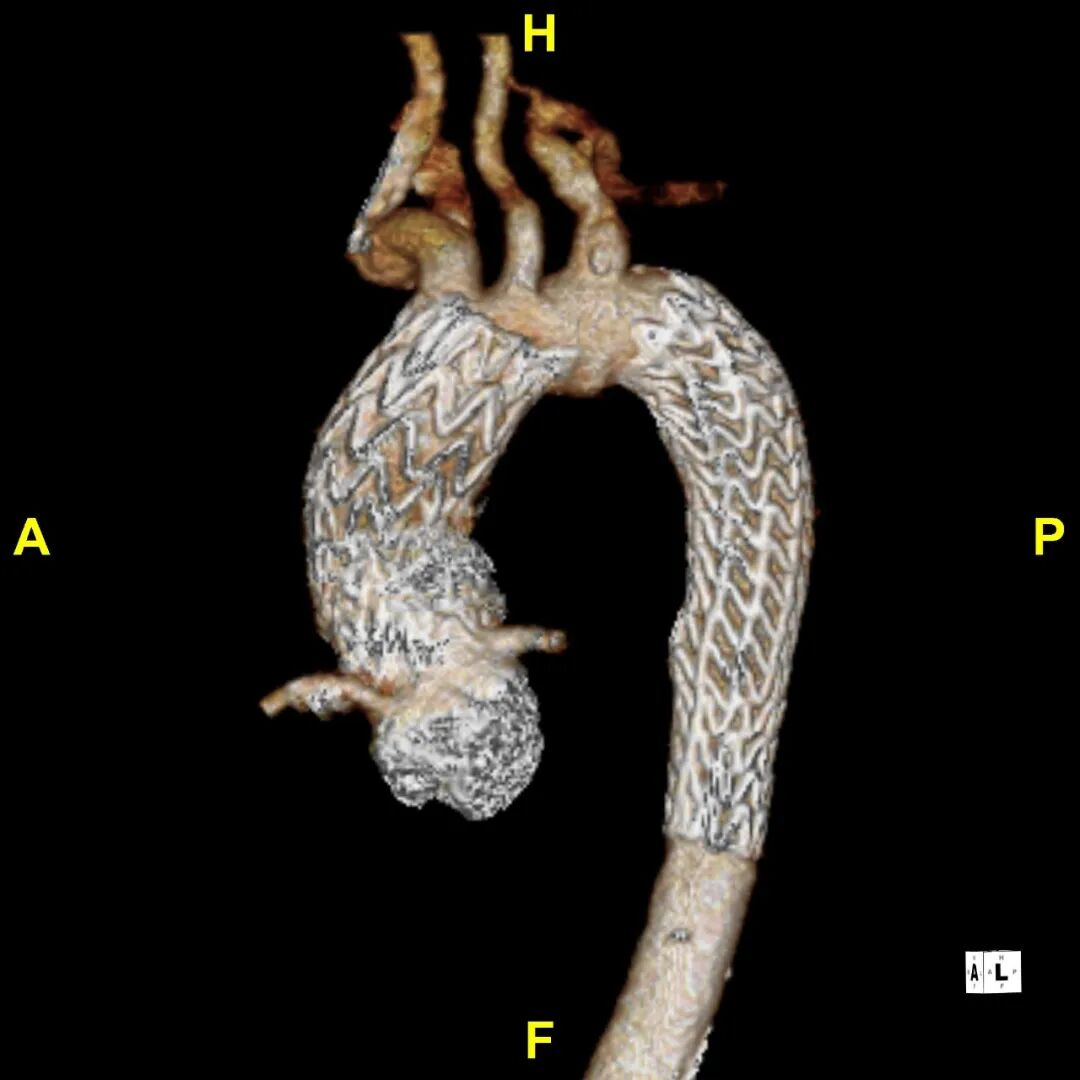

术前3D重建

术后随访

患者出院前进行CTA复查,可见溃疡隔绝完全,弓上分支血管及冠状动脉通畅。

术后3D动态

gore医疗怎么样「胸有乾坤」异“区”同“功” 精准定位——GORE® TAG® 可主动调控胸主动脉覆膜支架治疗升主动脉穿透性溃疡病例报道_https://www.jmylbn.com_新闻资讯_第21张

术后3D重建

gore医疗怎么样「胸有乾坤」异“区”同“功” 精准定位——GORE® TAG® 可主动调控胸主动脉覆膜支架治疗升主动脉穿透性溃疡病例报道_https://www.jmylbn.com_新闻资讯_第23张